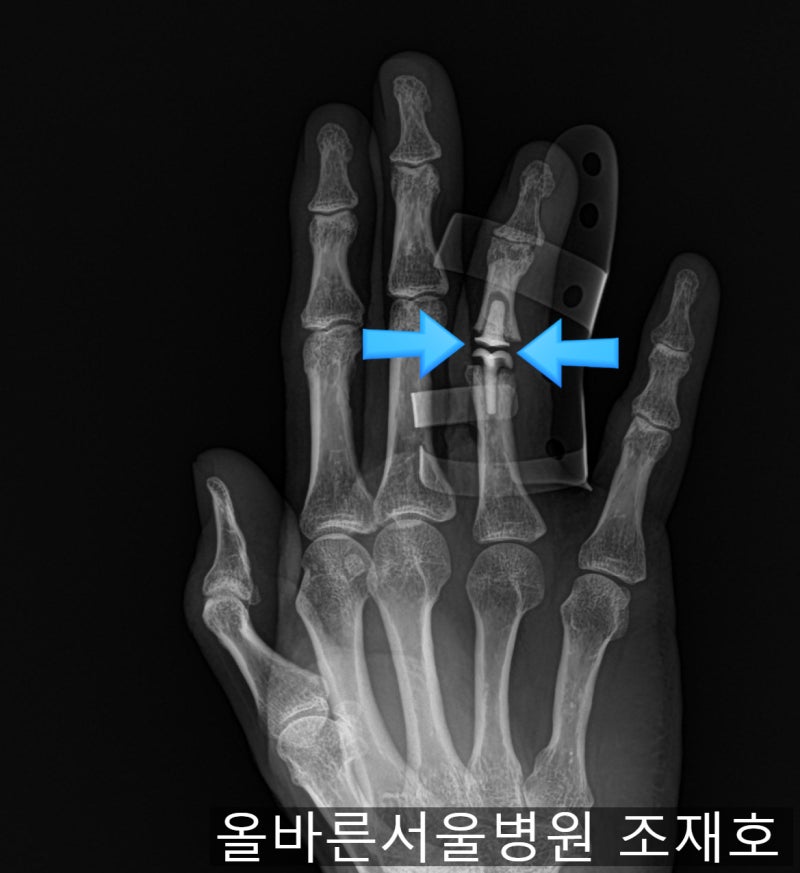

손가락이 움직이지 못하고 점점 뻣뻣해지고 관절 사이의 거리가 점점 좁아집니다. 뼈(파란색 화살표)가 나오고 있는데 관절이 좋지 않고 연골이 점점 손상되고 있는 것 같습니다(흰색 화살표). 수술 6개월 후 사진에서는 관절이 심하게 손상되어 새끼손가락까지 변형되어 외상성 관절염이 빠르게 진행되어 거의 모든 관절이 파괴되었습니다. 계속 관찰하였으나 관절염이 호전되지 않고 통증이 심해지며 관절의 운동범위가 감소하였다. 병원에서는 외상성 관절염이 너무 심해서 X-ray로는 안보이는 실리콘 인공관절을 해줬습니다. 이전에는 뼈가 관절염에 밀착되어 있었지만 실리콘 관절이 들어오면서 조금씩 뼈가 분리되는 것을 볼 수 있습니다. 이후 시간이 지남에 따라 실리콘 조인트 삽입으로 약간 넓어졌던 조인트 간격이 다시 좁아지는 것을 볼 수 있었다. 실리콘 인공관절 후 1년은 뼈가 다 붙고 딱딱해져서 손가락을 전혀 움직일 수 없었습니다. 이 경우 인정되었습니다. 둘째, 손가락을 움직일 수 없어 매우 불편하다 손을 펼 때 자신도 모르게 손을 치거나 누르면 손을 닫은 채로 있어야 한다. 그래서 인공적으로 열분해탄소를 사용하기로 하고 관절을 재수술하게 되는데 수술 중에는 인공관절을 위한 공간을 확보하기 위해 뻣뻣한 손가락 관절을 먼저 제거해야 합니다. 안에 있는 실리콘 커넥터를 제거합니다. 수술중에 잘려나갔지만 원래는 일체형으로 되어있어 가동관절이 아니고 실리콘이 부드러워서 손가락을 구부리면 휘어져서 계속 움직이는데 뼈가 부드럽다면 이렇게 붙여도 소용없다. 열분해 탄소 관절을 위한 공간을 확보하고 근위 지골에 파일을 사용하여 보철 관절이 삽입될 공간을 확보합니다. 파일은 인공 관절의 방향 및 회전 정렬을 모두 고려합니다. 그것이 골수 구멍에 있는지 측면에서 확인하십시오. 인공관절 검사기를 삽입하여 삽입할 인공관절의 크기와 방향, 인대의 균형을 확인합니다. 측면에서 핏을 확인하고 실제 인공관절을 삽입합니다. 옆에서 봐도 잘생김. 수술 후 사진에서 인공 관절이 제자리에 있는 것을 볼 수 있습니다. 측면 사진에서도 핏을 볼 수 있습니다. 따라서 열분해 탄소 보철물을 이용한 재치환 수술은 실리콘 보철물이 실패할 경우 좋은 해결책이 될 수 있습니다. 처음부터 실리콘 대신 열분해탄소 인공관절을 사용하는 것이 더 나을 수도 있다. 내과 건강정보 라이트서울TV https://youtu.be/Ssm8m_O9Pgc www.allbarunhospital.co.kr 강동구 천호동 라이트서울병원 성형외과, 건강검진, 가정의학과, 서울대학교 경력의료 staff People www.allbarunhospital .co .kr 서울시 강동구 양재대로 1525 바른서울병원 바른서울병원